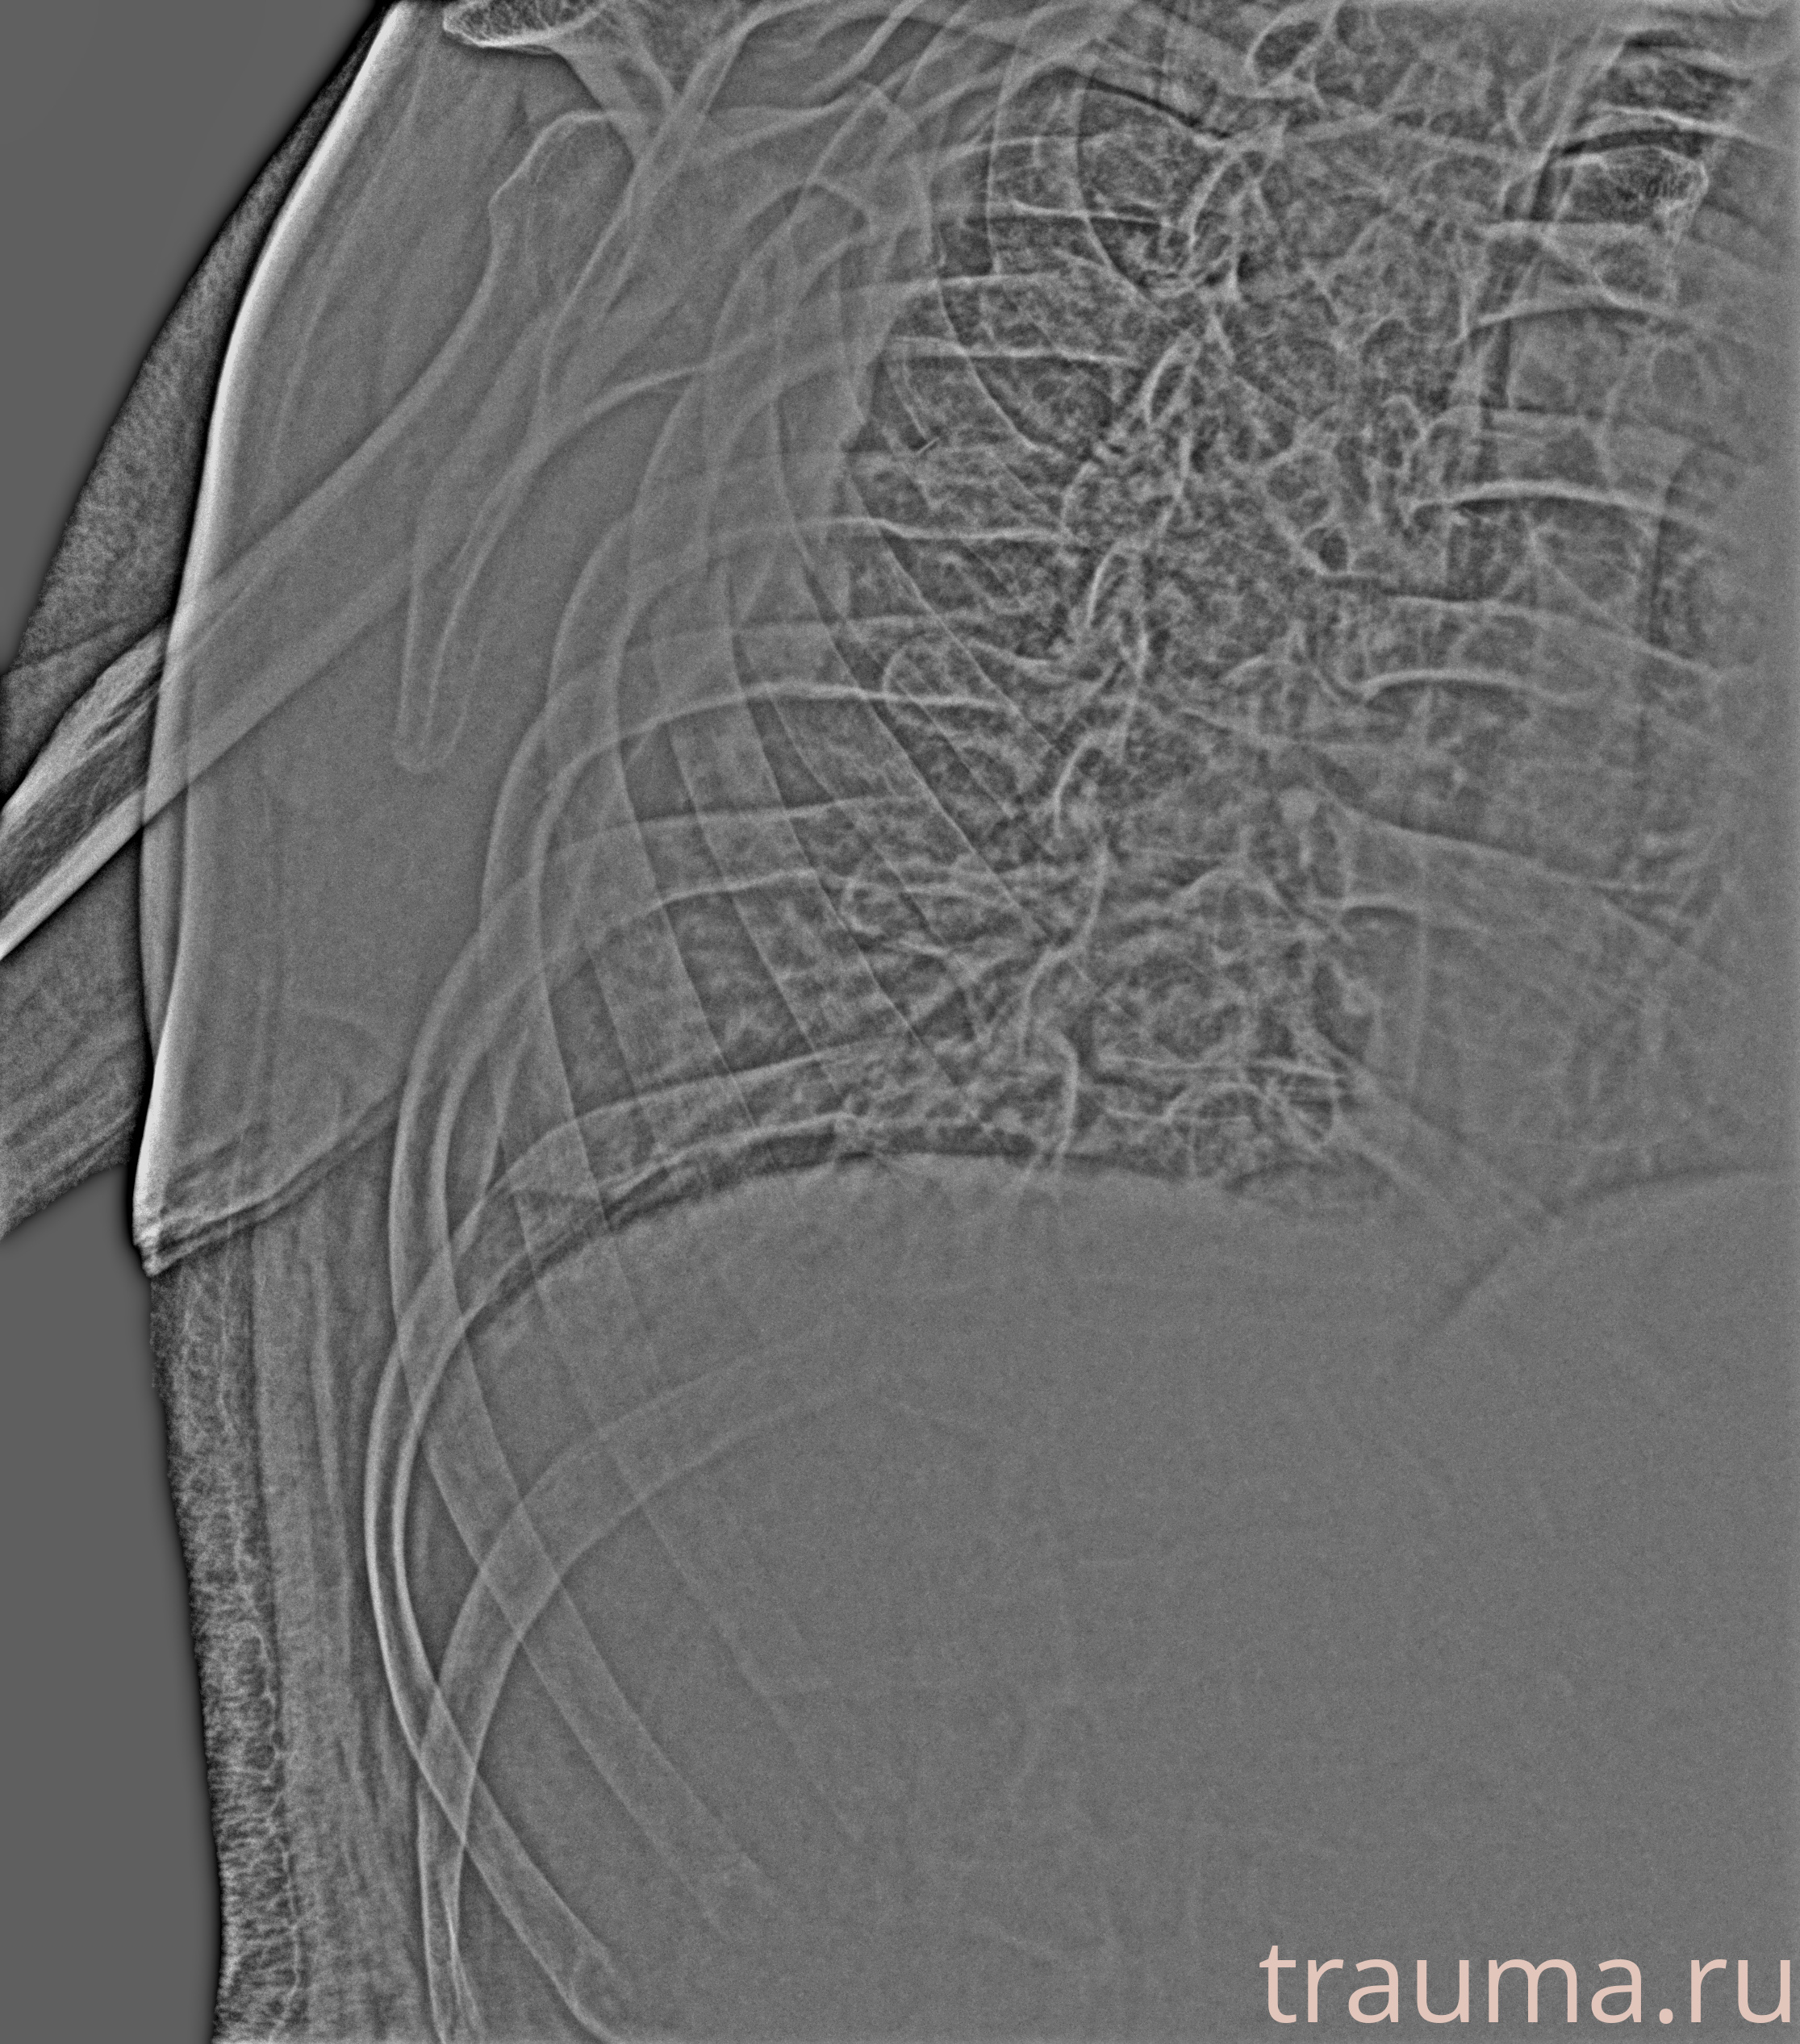

Рентген на дому: по вашему адресу приезжает врач-рентгенолог, травматолог-ортопед с мобильным рентгеновским аппаратом, проводит диагностику травмы или заболевания, делает необходимые рентгенограммы, дает рекомендации по дальнейшему лечению. Получить качественные снимки в домашних условиях возможно благодаря уникальной методике, разработанной МосРентген Центром для института  Склифосовского

при переломе шейки бедра и пневмонии от компании МосРентген Центр - партнера Института имени Склифосовского